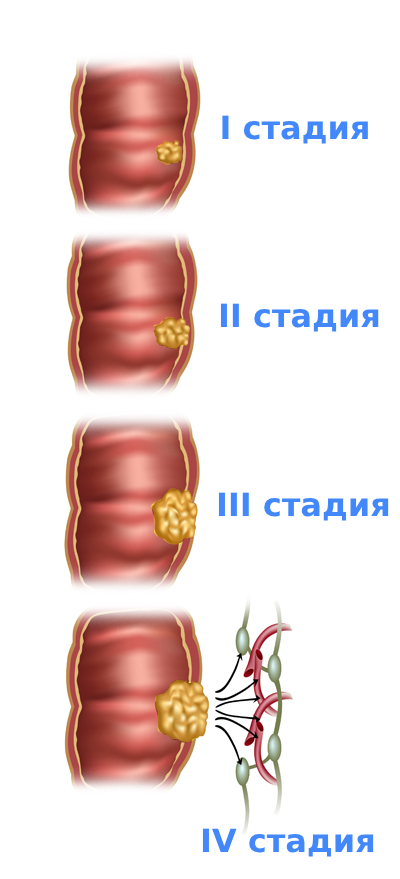

Стадии рака прямой кишки

Стадии рака прямой кишки определяются по международной системе TNM, утверждённой Всемирной организацией здравоохранения.

В этой классификации используется 3 параметра, каждому из которых присваиваются числовое значение:

T — размер опухоли и степень поражения ею стенки кишки:

- Т1 — образование распространяется на подслизистый слой стенки кишки;

- Т2 — опухоль затрагивает мышечный слой;

- Т3 — врастание неоплазии в субсерозную оболочку или неперитонизированную околокишечную клетчатку (для отделов кишки, покрытых брюшиной, опухоль Т3 не прорастает серозную оболочку);

- Т4 — неоплазия распространяется окружающие органы и ткани.

N — поражение близлежащих лимфатических узлов:

- N0 — поражения нет;

- N1 — поражены 1-3 лимфоузла;

- N2 — метастазы в 4 и более лимфоузлах.

M — наличие метастазов в отдалённых органах:

- М0 — отдалённых метастазов нет;

- М1 — есть отдалённые метастазы.

TNM-классификация помогает врачам определить степень развития заболевания и его тяжесть в каждом конкретном случае, чтобы выбрать подходящую тактику ведения пациента.

Стадия 1

Процесс ограничен подслизистым или мышечным слоем прямой кишки, не распространяется за их пределы. Метастазы в лимфоузлах, других органах отсутствуют. Стадия 1 считается самой благоприятной при своевременной диагностике и проведении хирургического лечения.

Стадия 2

На стадии 2А образование прорастает мышечный слой стенки прямой кишки, переходит на субсерозную оболочку или неперитонизированную околокишечную клетчатку. Для верхних отделов прямой кишки — опухоль не прорастает серозную оболочку. Окружающие органы при этом не страдают.

На стадиях 2B и 2С неоплазия прорастает стенку прямой кишки, распространяясь на соседние органы и ткани: висцеральную брюшину, мочевой пузырь, матку, влагалище, простату, крестец.

Регионарные лимфоузлы во всех случаях не поражены, метастазы отсутствуют. Лечение на 2 стадии также преимущественно хирургическое, однако может потребоваться дополнительная терапия для предотвращения рецидивов.

Стадия 3

Опухоль может находиться в пределах прямой кишки или распространяться на соседние ткани и органы, при этом у пациента обнаруживается поражение регионарных лимфоузлов. Метастазы в отдалённые органы на этой стадии отсутствуют.

Помимо хирургического лечения, обязательно проводится комбинированная терапия. Дополнительно назначают химиотерапию (или лучевую терапию), что улучшает прогноз и снижает риск повторного возникновения заболевания.

Стадия 4

Это наиболее поздняя стадия болезни. Она характеризуется наличием отдалённых метастазов в печени, лёгких, костях или других органах. Терапия на этой стадии часто паллиативная. Она облегчает симптомы, помогает улучшить качество жизни пациентов.